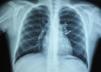

Aos 11 anos de idade, foi referenciado à Cardiologia Pediátrica por quadro de angor e dispneia de esforço com um mês de evolução. Na telerradiografia de tórax verificou-se a presença de calcificação arrendondada na porção superior esquerda da silhueta cardíaca (Figura 1). Realizou eletrocardiograma que não demonstrou alterações. O ecocardiograma revelou ectasia da coronária esquerda (4 e 5mm nos segmentos proximal e distal, respetivamente), sem alterações segmentares da contratilidade ou regurgitação mitral. Realizou cintigrafia de perfusão miocárdica com prova de esforço, durante a qual o doente referiu desconforto torácico no exercício máximo e o eletrocardiograma no esforço máximo evidenciou infradesnivelamento de ST em ii, iii, aVF, V5 e V6. A cintigrafia demonstrou, em esforço, hipoperfusão grave do ápex e segmentos ântero-septal, septo-apical e ântero-apical e moderada nos segmentos médio e basal das paredes anterior, inferior e infero-septal, correspondendo aos territórios das artérias descendente anterior esquerda (DA) e coronária direita (CD), com reversibilidade das imagens em repouso. Efetuou-se cateterismo cardíaco que revelou artéria DA ocluída na sua porção proximal a jusante de aneurisma calcificado e com enchimento retrógrado por circulação colateral a partir de ramos proximais da coronária esquerda (Figura 2), CD ocluída no seu segmento proximal com enchimento retrógrado circulação colateral a partir da coronária esquerda (Figura 3), e ventriculografia esquerda demonstrando boa função, sem alterações aneurismáticas do ventrículo.

A) Coronariografia esquerda - artéria descendente anterior esquerda ocluída distalmente a aneurisma calcificado (seta). B) Coronariografia esquerda - as setas indicam o aneurisma calcificado. C) Coronariografia esquerda - artéria descendente anterior esquerda ocluída com enchimento tardio, retrógrado (setas), por circulação colateral a partir de ramos proximais da coronária esquerda.